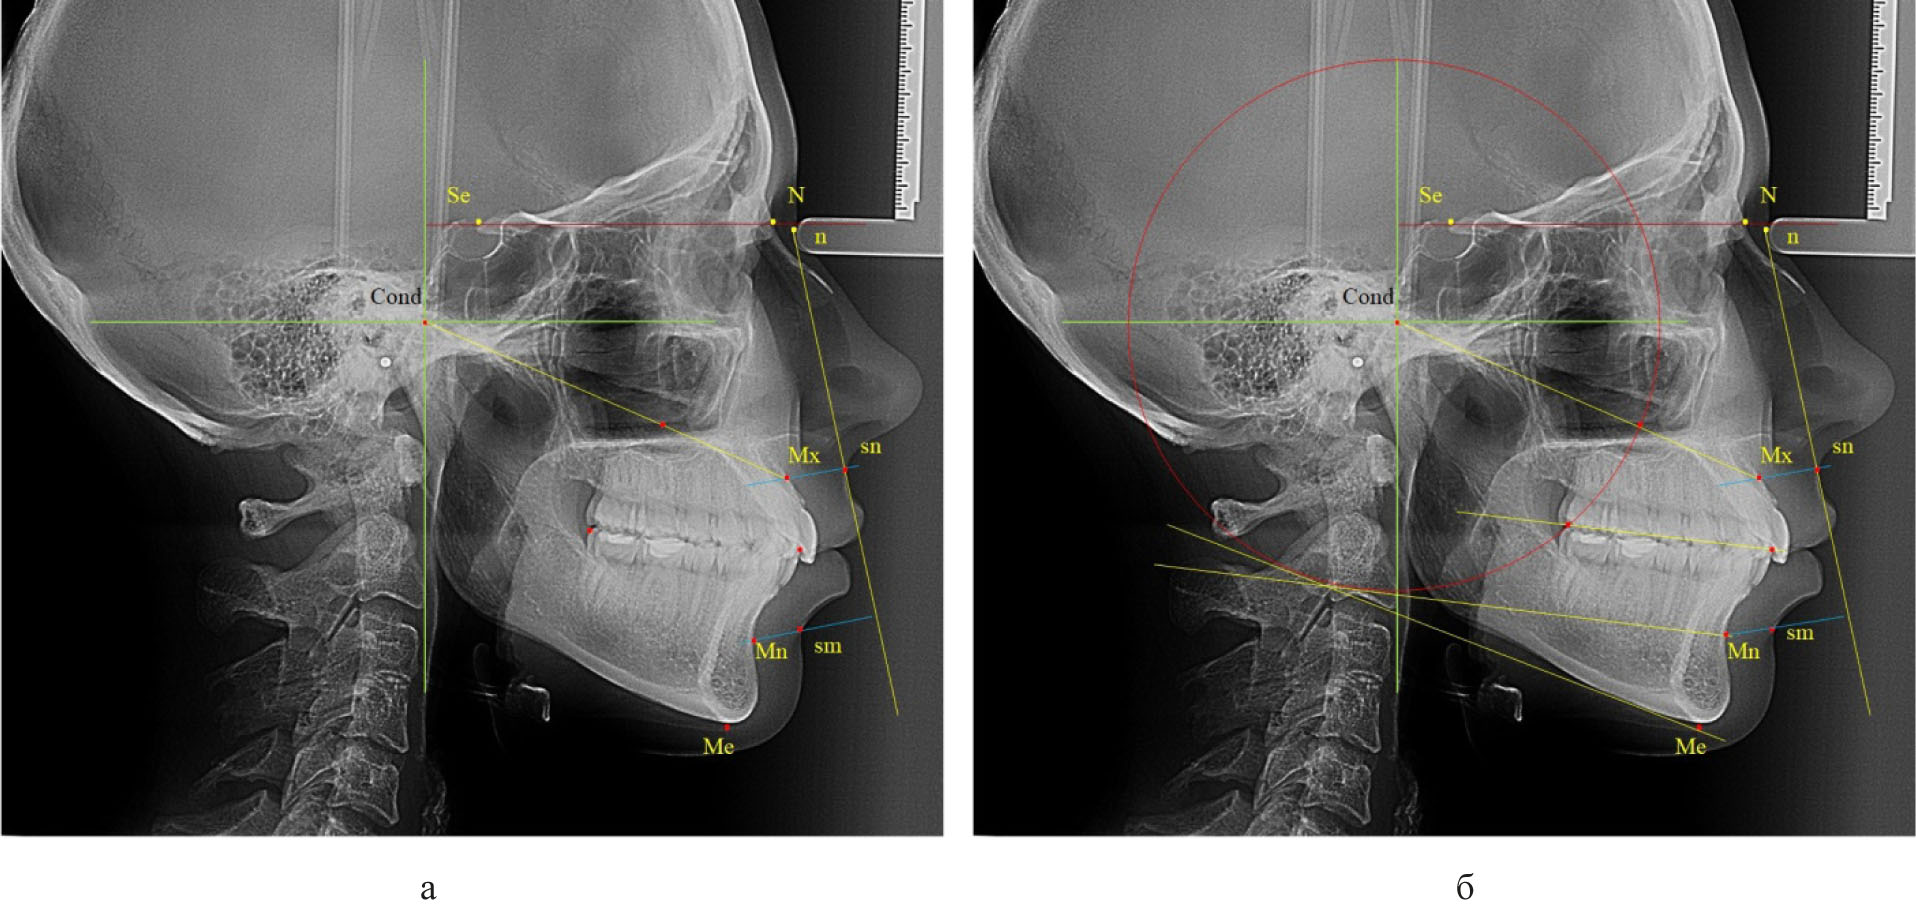

Учитывая тот факт, что на ТРГ были сложности определения точек апикальных базисов верхней и нижней челюсти, обозначаемых буквами «А» и «В», обусловленных наложением других структур, первым шагом алгоритма построения окклюзионной линии было определение стабильных ориентиров на передней поверхности челюстных костей. С этой целью через кожные точки назион и субназале проводили назально-субназальную вертикаль (n-sn). Перпендикулярно к ней через точку «sn» проводили линию до пересечения с передней поверхностью верхней челюсти и полученную точку обозначали как «Mx» (максиллярный ориентир). Аналогичным образом проводили линию через точку «sm» с обозначением на нижней челюсти мандибулярного ориентира «Mn».

Далее проводили построение суставного круга, радиусом которого было расстояние от точки «Cond» до задней окклюзионной точки «hPOcP» (рис. 3).

Рис. 3. Основные точки (а) особенности построения суставного круга и диагностических линий (б) для построения окклюзионной плоскости

Следует отметить, что окружность пересекала линию «Cond-Mx» и делила ее на два неравных отрезка. При этом расстояние от точки «Cond» до пересечения с окружностью было в 1,5 раза меньше размера «Cond-Mx», что может быть использовано в качестве ориентира построения суставного круга при отсутствии зубов жевательных сегментов или при аномалиях положения вторых моляров.

Касательная линия к нижней части суставного круга, проведенная из точки мандибулярного ориентира «Mn», как правило, была параллельна окклюзинной линии вне зависимости от типологических особенностей роста лица и челюстных костей.